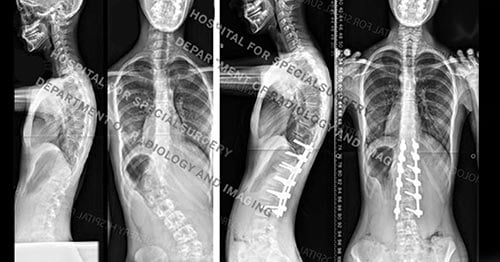

Figure 3. Posteroanterior (back-to-front) X-ray images showing a spinal curve in excess of 40° and then the same patient undergoing treatment with growing rods.